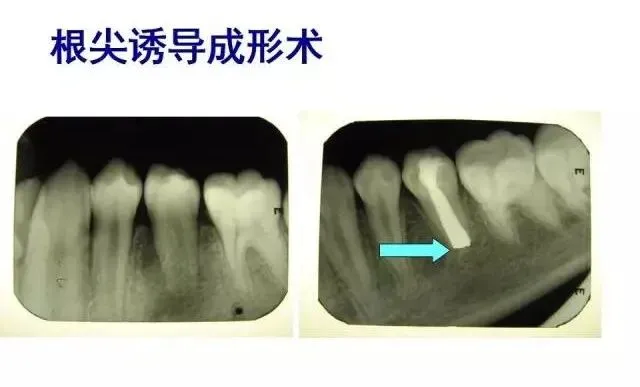

>PPT典藏 | 根尖诱导成型术

PPT典藏 | 根尖诱导成型术